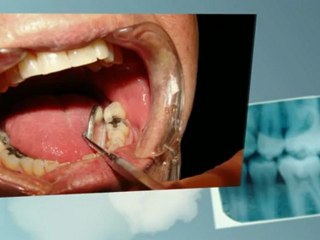

Implantaten in Apeldoorn: br Tel. 055-5346350 br br Implantaten in Apeldoorn: vakkundig, snel en professioneel door ervaren en deskundige implantoloog. br br In bijgaande video vertellen wij u meer over implantaten: br • Wat zijn implantaten? br • Waarvoor dienen implantaten? br • Hoe verloopt de behandeling voor het plaatsen van implantaten? br br U kunt bij ons terecht voor implantaten in de bovenkaak, alsmede voor implantaten in de onderkaak. Wij doen er alles aan om napijn bij uw implantaten te voorkomen. br br Neem voor implantaten in Apeldoorn vandaag nog contact op, via: 055-5346350. Ook als u wilt weten wat implantaten kosten. br br Wijsman en Koster Tandartsen br Ketelboetershoek 29 br 7328 JE Apeldoorn (Gelderland) br Tel.